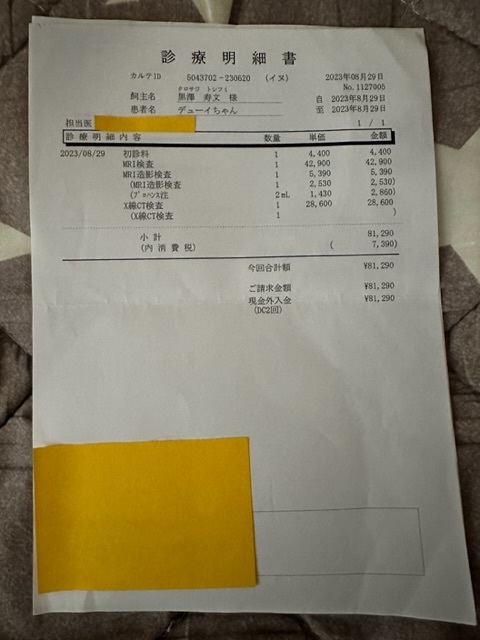

CTやMRIによる詳しい検査により

腰骨辺りの髄膜を包む膜が引っ張られ袋状になっている箇所がある事から麻痺や神経障害があり

排尿や排便に障害を起こしている為、改善する手術を行う。

腰骨も陥没が見受けられ陥没した所から神経の膜を引っ張っているような状態だそうです。

下の写真の赤い○の中にある三角の物は本来無いもので、引っ張られた膜が映ったものです。

※上記は大学病院で頂いた診断書

※下記は初診かつ、会陰形成術をして頂く動物病院より発行して頂いた診断書、治療計画書

実際にかかった治療費

大学病院での検査